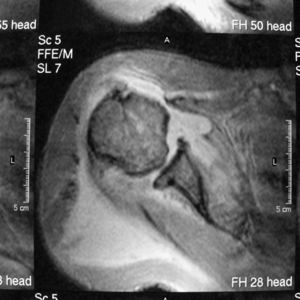

Los datos de laboratorio más relevantes fueron leucocitosis (14,2×109) con neutrocitosis (84%), macrocitosis (VCM de 99fl), discreta trombopenia (112×109/l), GPT-ASAT (78UI/l; valores normales<45) y GGT (115UI/l; valores normales<65). Tanto en los 3 hemocultivos como en el derrame articular del hombro derecho, donde la tinción de Gram mostró cocos grampositivos, se recuperó Staphylococcus epidermidis. La radiografía de tórax mostró aplanamiento de las cúpulas diafragmáticas, calcificaciones en el cayado aórtico y aumento de la trama broncovascular. La ecografía visualizó rotura completa y retracción de los tendones subescapular y supraespinoso, subluxación del tendón de la porción larga del bíceps, abundante derrame articular y bursal de ecogenicidad heterogénea e irregularidad de la cabeza humeral. Estos hallazgos se confirmaron mediante RM, en la que, además, se comprobó un incremento de la captación del contraste de gadolinio tanto en la cabeza humeral como en el área glenoidea (fig. 2). No hubo signos de endocarditis en el estudio ecocardiográfico.